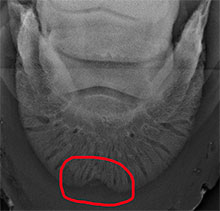

Eine Hornsäule beschreibt eine Verdickung an der Innenfläche der Hornwand, die von Kronrand bis Tragrand reichen und säulen-, kegel- oder leistenförmig sein kann. Sie entsteht nach Wunden der Kron- oder Wandlederhaut durch z.B. Traumata wie Kronentritte oder auch Hornspalte. Diese Verletzungen führen, ob eitrige oder nichteitrige Pododermatitis, zu einer vermehrten Durchblutung des Gebietes und damit zu einer übermäßigen Hornproduktion. Dabei ist die Vorderwand häufiger betroffen als die Seiten- oder Trachtenwände. Vorder- und Hintergliedmaßen können gleichermaßen eine Hornsäule aufweisen.

Nicht immer ruft eine Hornsäule eine Lahmheit hervor, manchmal wird sie zufällig durch den Schmied beim Bearbeiten der Hufe festgestellt. Mittelgradige Lahmheiten sind jedoch charakteristisch für Hornsäulen, die schon mit einer Usur (= Einziehung) des Hufbeines einhergehen, und können am Hinterbein aussehen wie ein Hahnentritt. Meistens haben die betroffenen Pferde eine vermehrte Pulsation der Mittelfußarterie und eine Verbreiterung der weißen Linie nach innen in diesem Bereich. Im Röntgenbild sieht man Lufteinschlüsse und im vorangeschrittenen Stadium eine charakteristische Usur des Hufbeines. Diese ist irreversibel, was bedeutet, dass sich der Knochen davon nicht mehr erholen wird.